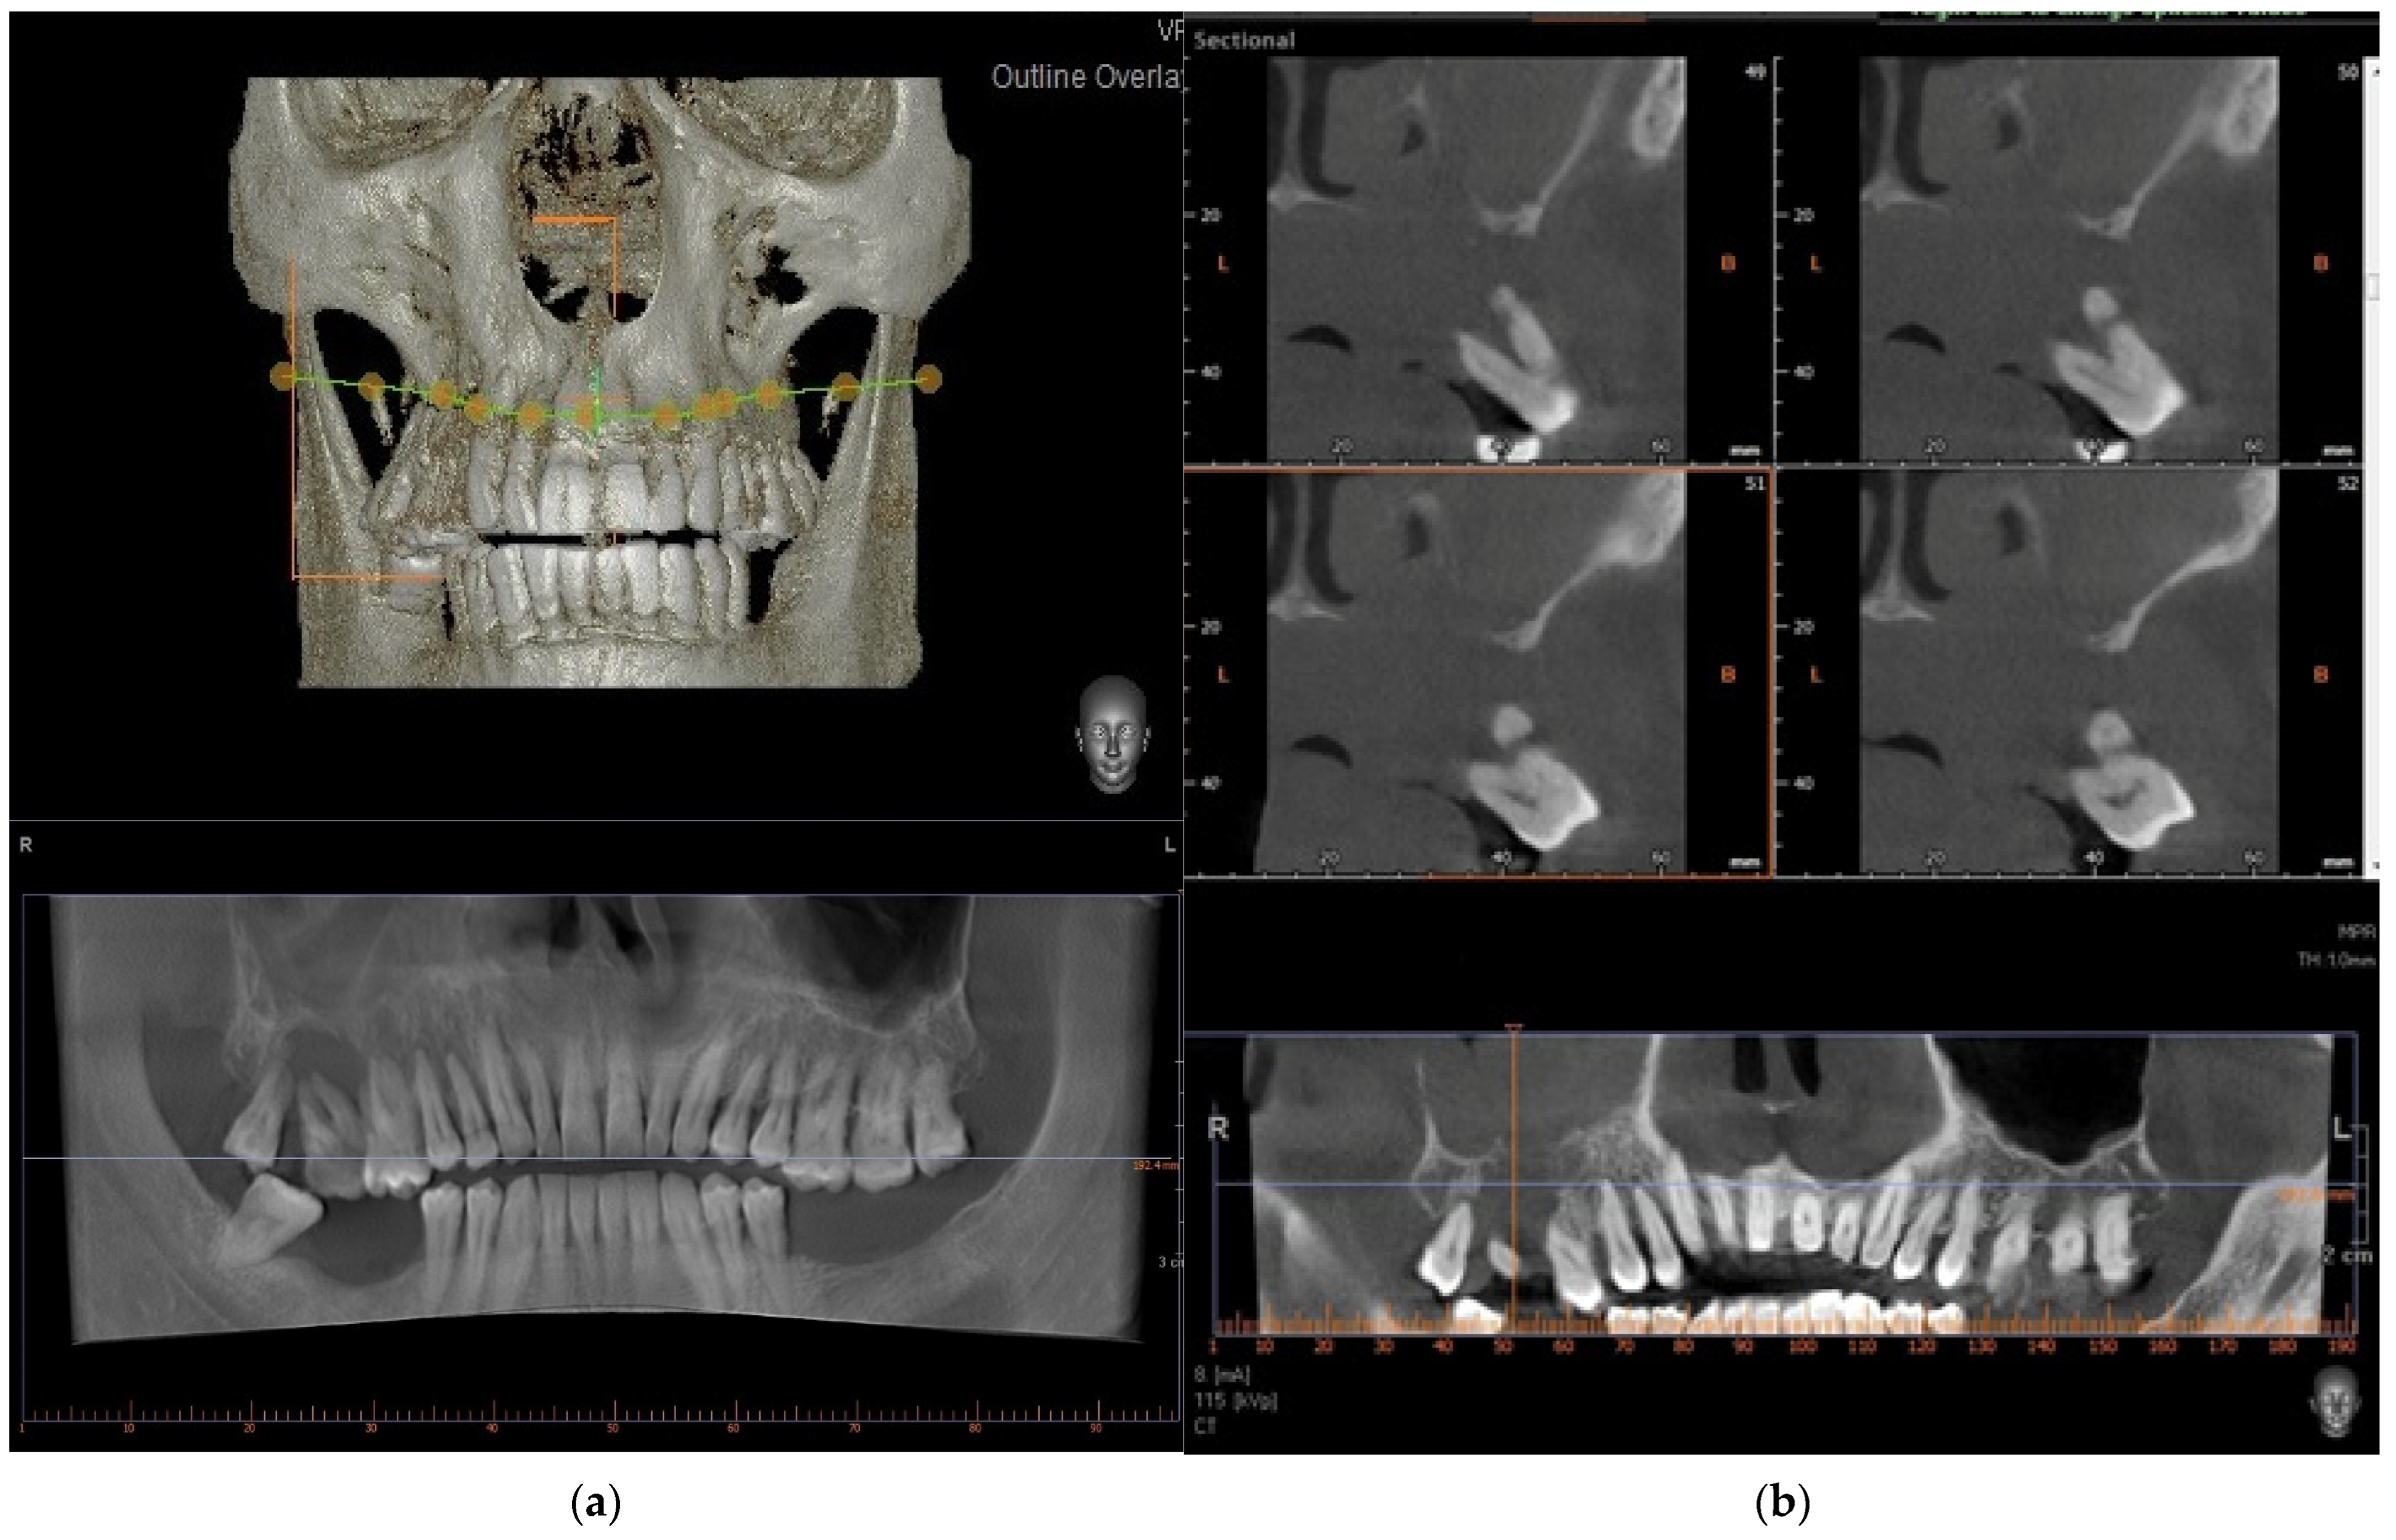

Figure 2.

Preoperative radiograph images. In image (a) no bone destruction is detectable in the 3D reconstruction. Below, a simil panoramic image shows bone destruction in the upper right molar region (a). CBCT reveals the osteolytic change in the upper molar region, involving the hard palate (right) (b).